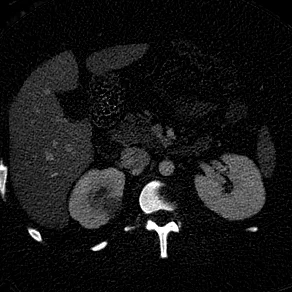

Pyelonephritis

Right flank pain.

Routine CT shows very subtle hypodensity in right kidney.

Iodine map makes this much more obvious. E coli grew on urine culture.